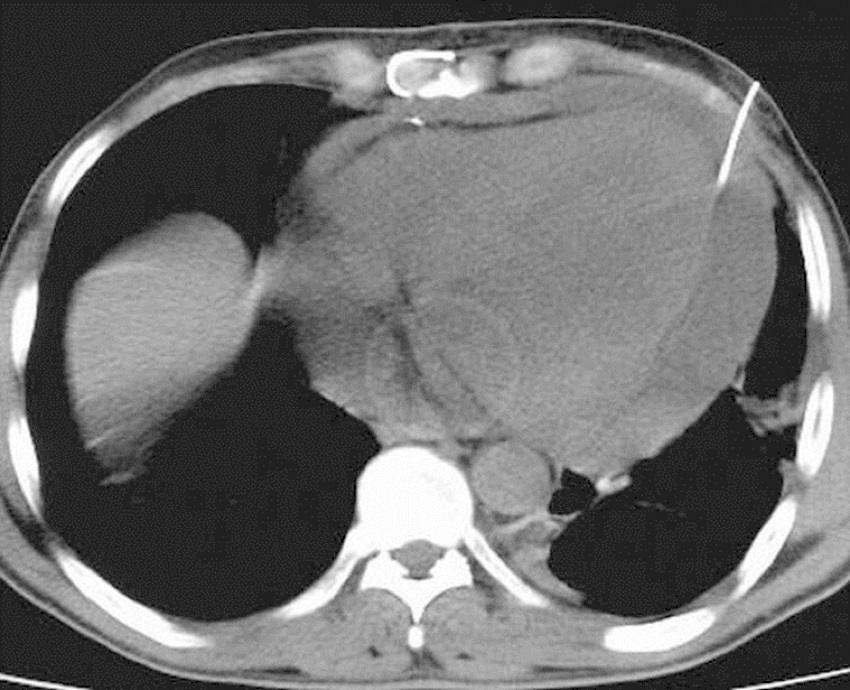

Having been colored and disinfected, the marked area was covered with sterile drapes. As a local anesthetic agent, 2% lidocaine was used. Then, an 18 G needle with negative puncture was entered to the pericardial cavity, the needle was fixed at the level of liquid aspiration, and the CT was taken again to reaffirm the needle's position (Figure 2). After confirming that it was in the intrapericardial space, the liquid was aspirated and evaluated. If hemorrhagic characteristics were thought to be possible after confirming that the blood defibrinated, a 0.035" guidewire was sent to the pericardial cavity through the needle (Figure 3). The needle was removed and the CT was taken; after confirming that the guidewire was in the intrapericardial cavity, an 8 or 10 F nephrostomy catheter was advanced into the pericardial cavity through a catheter guide. A three-way tap was installed in the tip of the catheter and the liquid was poured into a 50 ml syringe. The catheter was identified and it was connected to the closed underwater drainage system (Figure 4).